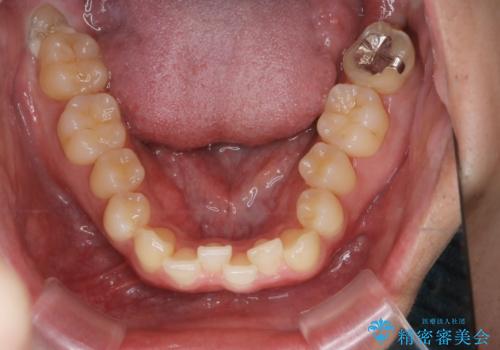

【クリア装置】八重歯とがたつきを綺麗に

- 上の八重歯と下の歯のがたつきを主訴に来院されました。

矯正検査の結果、抜歯はせずに

臼歯を遠心移動させ、歯列をワイヤーで整えることでスペースを確保し、IPR(歯と歯の間を削る処置)を加えて歯並びを綺麗にする治療計画を立てました。

歯の移動にオープンコイルとMI(歯肉に埋入するネジ)を用いました。

非抜歯矯正だったこともあり、1年半以内という短い期間で矯正を終了することができました。

気にされていた八重歯とがたつきが綺麗に改善されました。